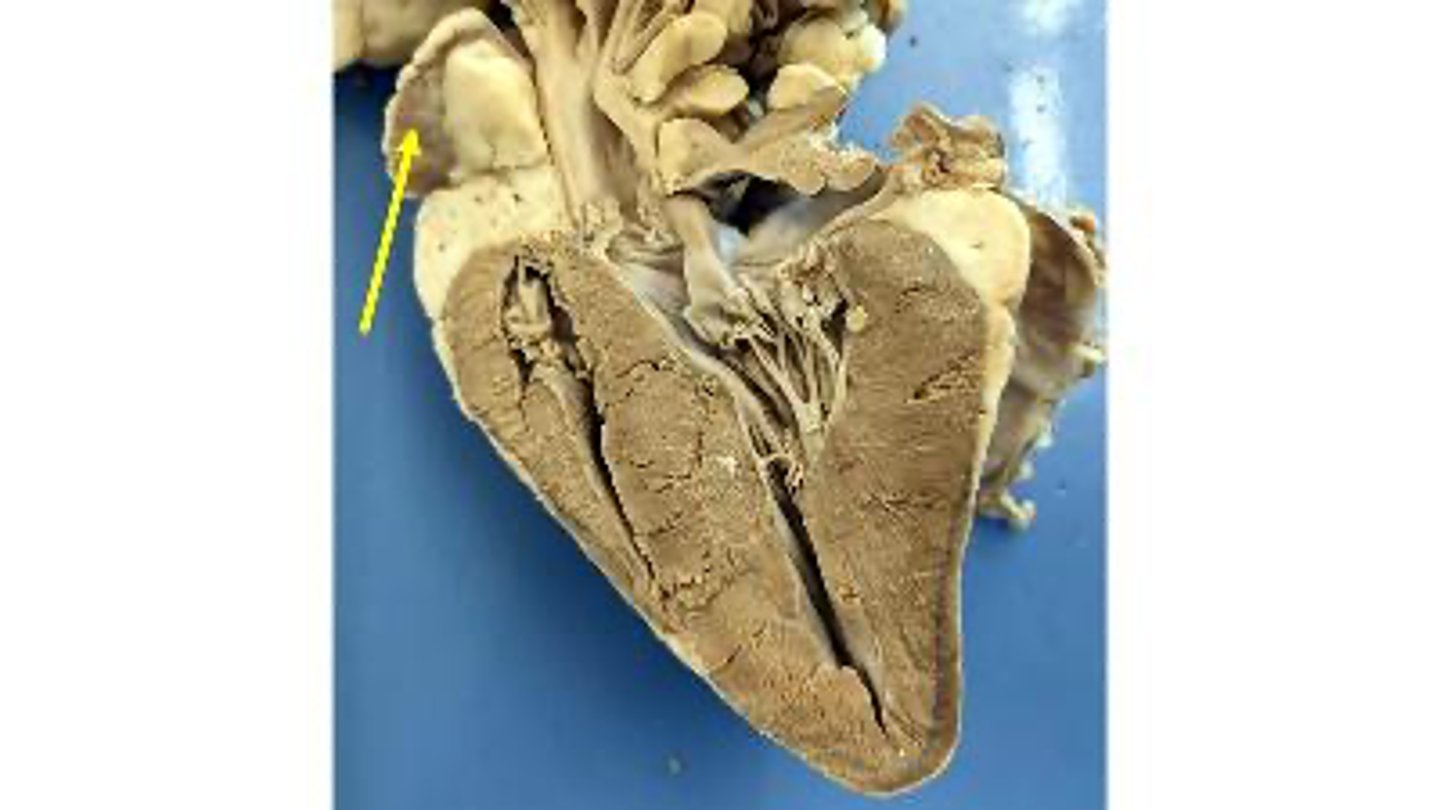

Superior vena cava

what is this

Ligamentum arteriosum